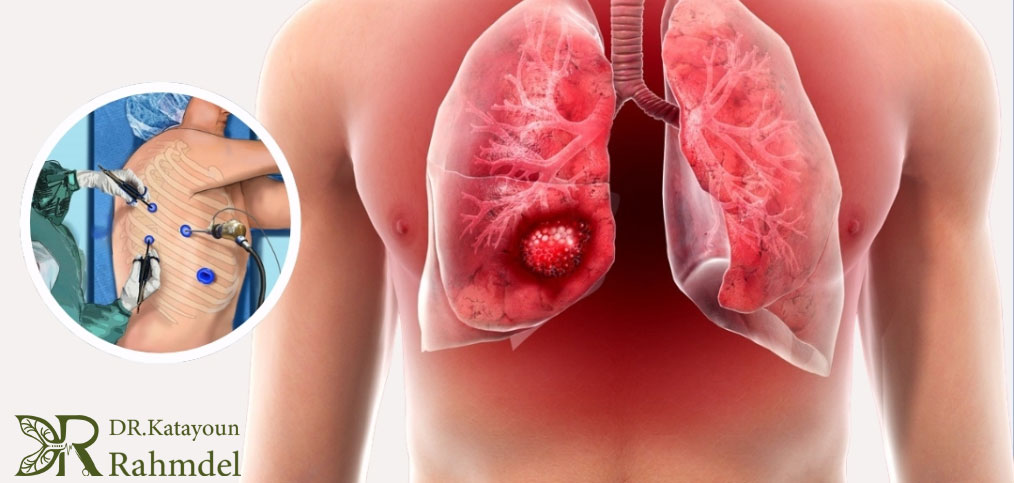

جراحی

جراحی بهعنوان اصلیترین روش درمانی در مراحل اولیه سرطان ریه و زمانی که بیماری به دیگر اندامها گسترش نیافته است، کاربرد دارد. انواع جراحی شامل لوبکتومی، پنومونکتومی یا جراحیهای محدودتر است و هدف آن برداشتن کامل تومور و جلوگیری از بازگشت بیماری میباشد. جراحی موفقیتآمیز نیازمند تجربه و مهارت بالا در جراحیهای توراکس است.

ولاووتراپی و جراحیهای کمتهاجمی

پیشرفتهای تکنولوژیک امکان انجام جراحیهای کمتهاجمی و با آسیب کمتر به بافت سالم را فراهم کرده است. این روشها معمولاً به کاهش درد، کاهش طول دوره نقاهت و بازگشت سریعتر بیمار به زندگی عادی کمک میکنند و با مهارت جراح توراکس میتوان بهترین نتیجه درمان را کسب کرد.

اهمیت انتخاب جراح توراکس باتجربه

در درمان سرطان ریه، یکی از مراحل اصلی، برداشتن تومور یا بخش مبتلا در ریه است. این عمل پیچیده نیاز به مهارت بالا، آشنایی با تکنیکهای کمتهاجمی و تجربه در مدیریت عوارض احتمالی دارد. ویژگی های بهترین جراح توراکس عبارت است از: